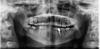

diesel87 Опубликовано 23 ноября, 2012 Поделиться Опубликовано 23 ноября, 2012 Вечер добрый коллеги, делаю первые шаги в имплантологии, планирую на операцию пациента (снимок ниже) в области 46, удален 2 года назад, хочу услышать ваше мнение, и также что думаете по поводу 47? Хватит ли места для коронки 46? Спасибо! Ссылка на комментарий

Алексей000_36_VRN.RU Опубликовано 23 ноября, 2012 Поделиться Опубликовано 23 ноября, 2012 Я пациентам предлагаю уд 48 дистализацию 47 и интрузию 16, если не хочет, то тогда возникает широкая апроксимальная зона между 47 и импл 46 большой треугольник, где парад проблемы могут быть. Как вариант еще можно пришлифовать медиально 47 и окклюзально 16, но на 47 окклюхионные контакты все равно будут не правильные.... Ссылка на комментарий

diesel87 Опубликовано 23 ноября, 2012 Автор Поделиться Опубликовано 23 ноября, 2012 не знаю зачем я написал про 45)) да, 47 и 16.Измерил в программе, по ОПТГ в области 46, 12мм до канала с запасом в 1 мм. Ссылка на комментарий

jm3300 Опубликовано 24 ноября, 2012 Поделиться Опубликовано 24 ноября, 2012 не знаю зачем я написал про 45)) да, 47 и 16.Измерил в программе, по ОПТГ в области 46, 12мм до канала с запасом в 1 мм.а по ширине без проблем? Ссылка на комментарий

diesel87 Опубликовано 24 ноября, 2012 Автор Поделиться Опубликовано 24 ноября, 2012 а по ширине без проблем?Без проблем, ширина хорошая Ссылка на комментарий

diesel87 Опубликовано 24 ноября, 2012 Автор Поделиться Опубликовано 24 ноября, 2012 Как на счет такого плана: удаляем все восьмерки, пришлифовываем 47, 16, имплантируем. Ссылка на комментарий